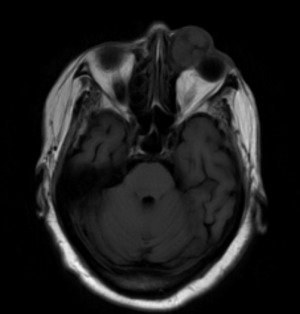

Given the difficulties of assessing lacrimal sac papillomas with external exam, imaging studies are an important component of their diagnosis and evaluation of their extent. Smooth masses can be seen on CT or MRI, with a characteristic heterogeneous signal on the latter being useful for differentiating from more homogenous lymphoid tumors. More broadly, dacryocystography can also be used to reveal the presence and location of lacrimal sac masses like papillomas, which can show up as a characteristic protruding defect in tumors extending into the lumen, though this is not a widely used study.